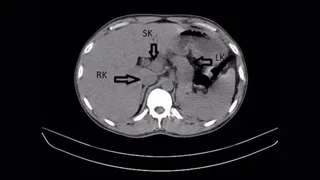

A parasite never before seen in humans was behind a woman's lung infection, organ damage and forgetfulness

By Mindy Weisberger published

A woman developed a persistent infection, and doctors couldn't pinpoint the cause for many months.